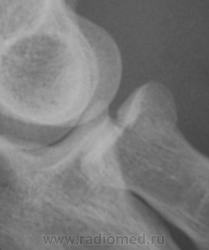

Рентгенограмма в прямой проекции.

Фрагменты с увеличением.